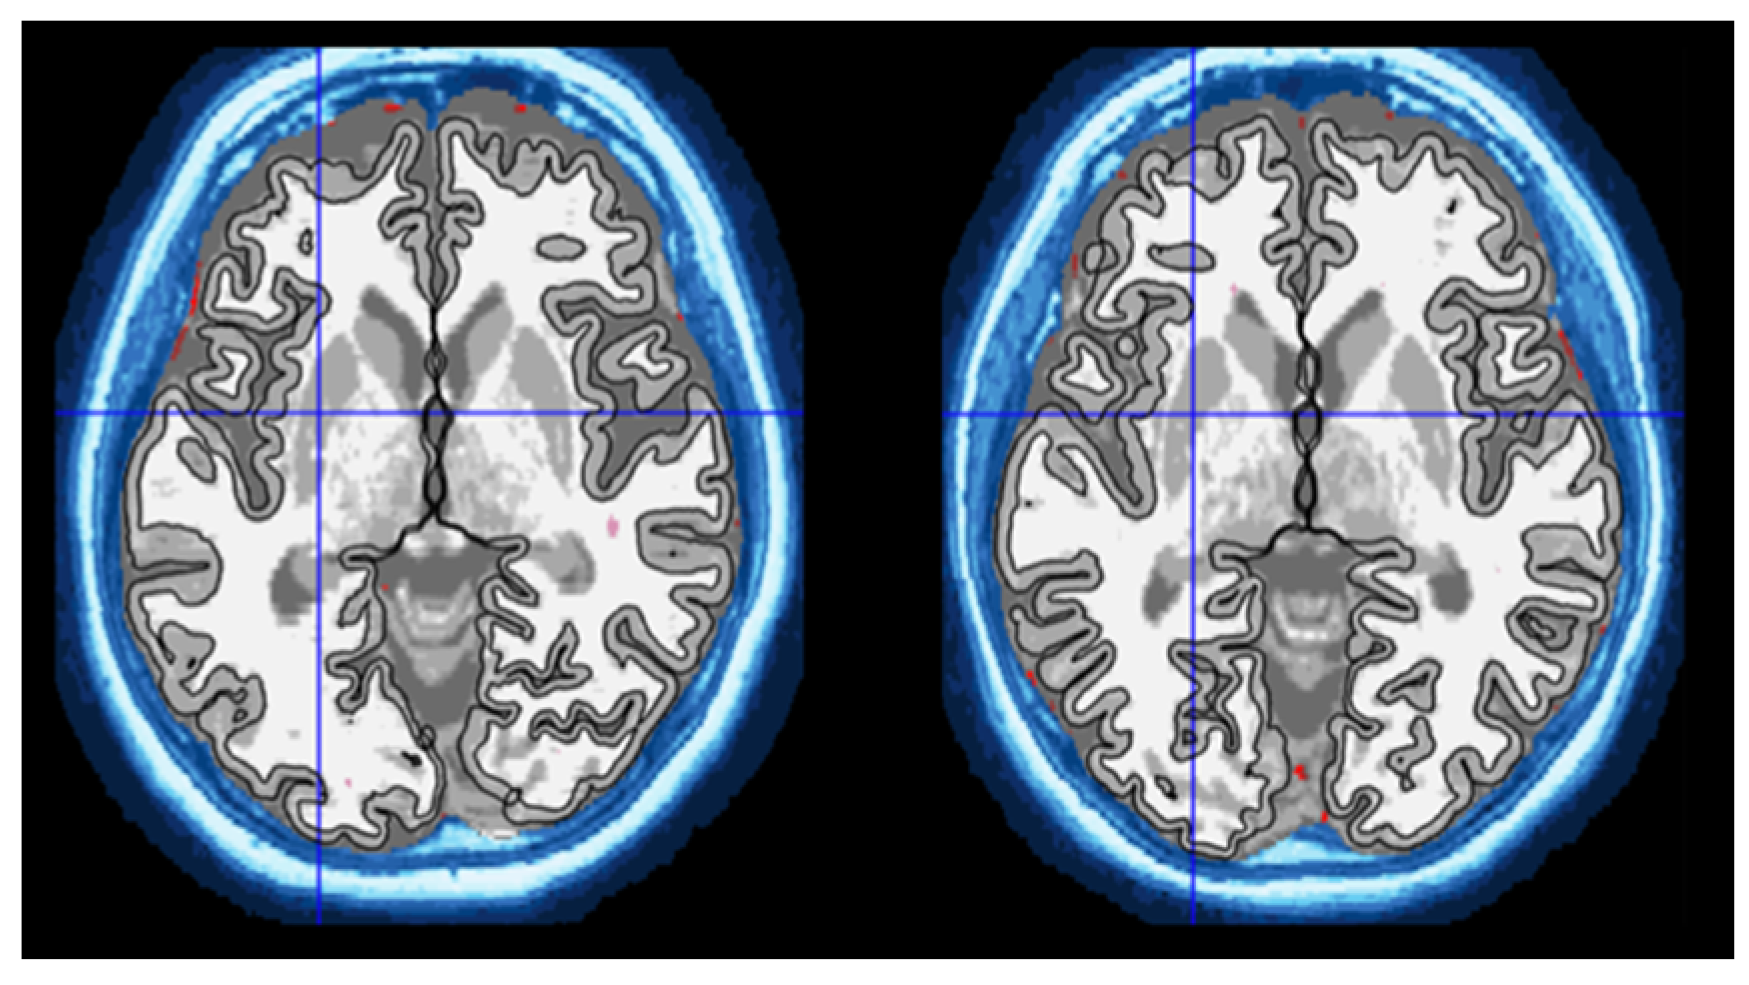

2.3.1. Volume Measurement Using Computational Anatomy Toolbox (CAT12) for Statistical Parametric Mapping (SPM12)

2.3.2. Volumetric Measurement Using volBrain